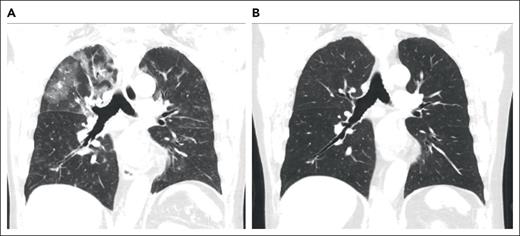

A 73-year-old man with a history of myelodysplastic syndrome, who received a nonmyeloablative allogeneic peripheral blood stem cell transplant (PBSCT), presented with progressive dyspnea, a nonproductive cough, and hypoxemia a year after HCT. Weeks before presentation, the patient was newly diagnosed with cGVHD of the skin. A chest computed tomography (CT) scan showed upper lobe predominant ground-glass opacities in a subpleural and peribronchovascular distribution (Figure 1A). The patient was treated for infectious pneumonia with levofloxacin without improvement. Clinical history did not reveal an antecedent exposure to medications associated with OP. Bronchoscopy with bronchoalveolar lavage (BAL) was performed, and microbiology culture results for bacterial, fungal, and viral pathogens were negative. On the basis of a lack of association with known pulmonary toxic medications or infectious agents, HCT-OP was diagnosed, and prednisone (1 mg/kg per day) was initiated with a slow taper over 4 months. The patient’s clinical symptoms rapidly resolved, including his skin cGVHD, and radiological improvement was achieved (Figure 1B).

Representative coronal images from a noncontrast chest CT scan. (A) CT scan of the chest, demonstrating a right-sided upper lobe–predominant, peripheral ground-glass opacity at the diagnosis of organizing pneumonia. (B) CT images after 4 months of treatment with prednisone, demonstrating resolution of opacities.